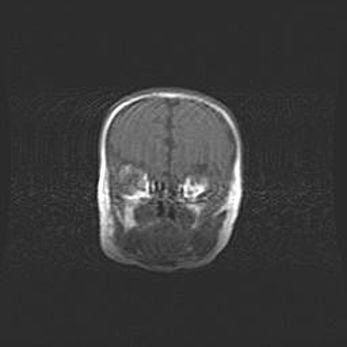

Подострая гематома правой гемисферы мозжечка.

Наружная гидроцефалия.

Возраст: 15 дней

Вес: 3100 г

Пол: женский

Окружность головы: 37 см

Срок гестации: 35-36 недель

При открытой наружной форме гидроцефалии у новорожденных расширяются и переполняются субарахноидные пространства.

Кровоизлияния в мозжечок имеют две клинико-анатомические формы: полушарные гематомы и кровоизлияния в червь.

К появлению этой патологии может привести: повреждения головного мозга, возникающие в результате асфиксии и гипоксии плода при беременности, или травмы во время родов. Редко гематома мозжечка может быть результатом первичной коагулопатии и сосудистой мальформации, диссеминированном внутрисосудистом свертывании, изоиммунной тромбоцитопении.